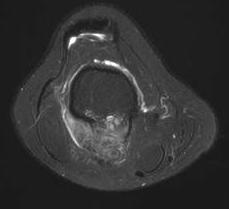

MRI

Parosteal osteosarcoma anterior tibia